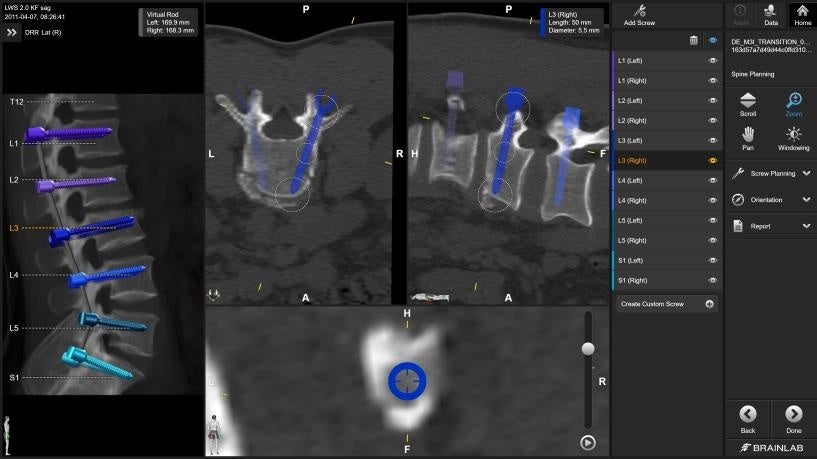

【Brainlab Elements】

特定の症例に特化した複雑な手術計画ワークフローに対し、自動化されたソリューションを提供する手術計画ソフトウェアです。

病変の輪郭描出などの画像処理から手術計画に至るプロセス全体における、高度に限定された個々のタスクを、連携する一連のElementsソフトウェアがカバーし、高精度な手術計画を短時間で作成できます。また、ユーザーのニーズに合わせて必要なソフトウェアのみ選択可能です。Brainlab Elementsは、ロボットを用いない通常の手術にも対応するほか、一連のデジタル手術製品と併用することにより、一貫性のあるエンドツーエンドのソリューションを提供します。